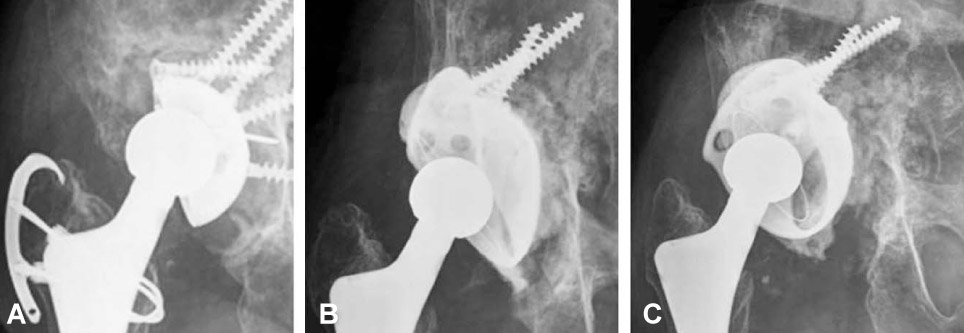

Thirty-six acetabular revisions were performed in 36 patients with use of the reinforcement ring and structural or morselized allograft, between 1997 and 2005, in thirty-six patients. According to the AAOS classification, thirty-four cases of acetabular defects were Ttype III, and two were Ttype IV. Mean follow-up period after surgery was 7.2 years.

The mean Harris hip score was 92.3, which was significantly increased compared with the preoperative score. (p<0.001). There were five failures: a case of aseptic loosening of Muller ring, two cases of infection (5.4%) and two cases of hip dislocation (5.4%). Graft incorporation and bone remodeling occurred successfully in all hips, but in the case of aseptic loosening in which the ring fixation had been inadequate at the time of surgery. The success rate was 91.7% with a mean follow-up of 7.2 years, if the cases of revision or loosening of the component were classified into failure cases.

Patients treated with acetabular revision with three kinds of reinforcement ring had reconstitution of periacetabular bone stock as well as good clinical and radiographic results. For the good results, the secure implant fixation during the surgery should be confirmed and we should completely understand the characters of the each kinds of reinforcement rings.